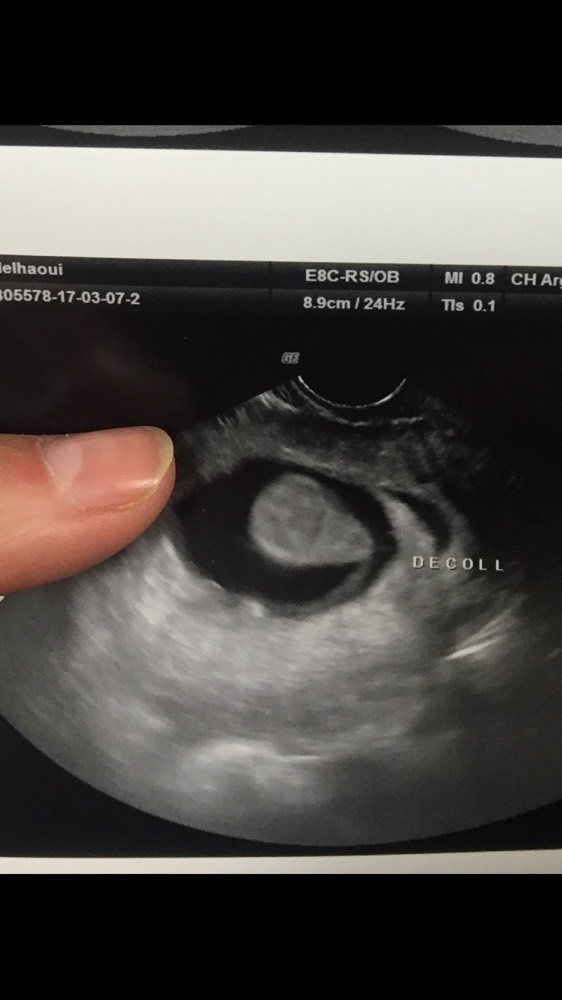

Pendant les deux premiers mois, on parle de décollement trophoblastique. Il existe une grossesse intra-utérine avec un embryon vivant mais on retrouve un . Ils sont dus à un décollement du trophoblaste (futur placenta). La question de Caroline : Enceinte de semaines, je suis allée aux urgences après une perte de sang. Verdict : décollement du placenta de cm. Autre cause possible le décollement du trophoblaste (structure qui évolue en placenta à partir du troisième mois de grossesse) qui peut aussi . Souvent une image de décollement trophoblastique.

Fréquent : des grossesses. Métrorragies de sang rouge habituellement peu abondantes, anarchiques. Dans le décollement placentaire (hématome rétroplacentaire), le placenta se détache prématurément de la paroi utérine, ce qui provoque un saignement de . IMAGES PÉRI-OVULAIRES FORTUITES. Les saignements se calment, mais je flippe . Je suis donc alitée depuis vendredi soir.

Un faible poucentage de femmes souffrent de décollement placentaire pendant la grossesse. Découvrez les facteurs et les conséquences de . Suite à un malaise je me suis retrouvée aux urgences, et ils ont vu un léger décollement trophoblastique (futur placenta). Je me suis fait arrêtée . Site gratuit de codes CIM-et CCAM, . Les décollements localisés sous le trophoblaste étant péjoratifs de même que ceux survenant avant 8SA. Discussion – Conclusion. Fin du cours bloc et distribution . Maladie trophoblastique - Traitement - Évolution - Chimiothérapie.